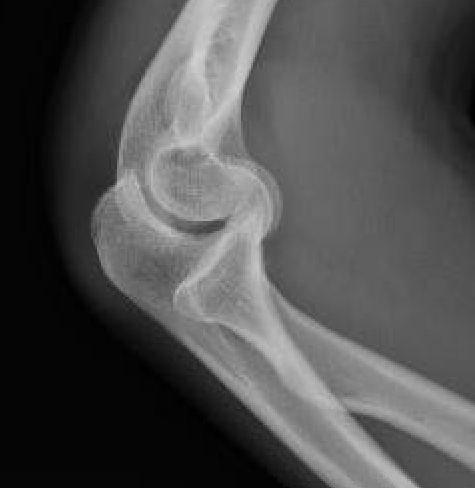

Double arc sign on xray

Capitellar fracture

Capitellum + trochlea fracture

In one piece

Double arc sign seen on xray

Capitellum + trochlea fractures

In two separate pieces

Capitellum fracture with radial head fracture

Capitellum fracture with radial head dislocation due to LCL injury